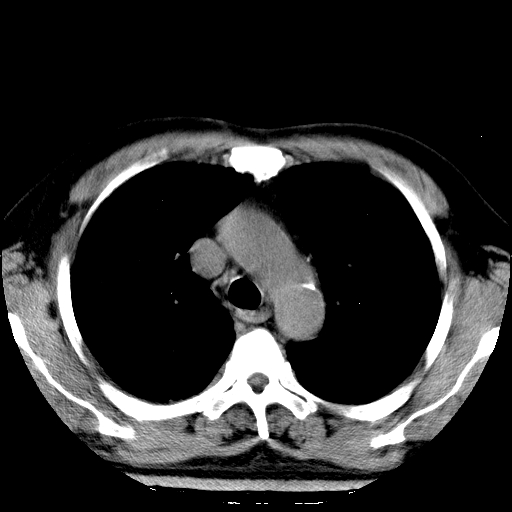

标题: CT21804:男,65岁,咳嗽、咳痰、发热5天。 [打印本页]

男,65岁,咳嗽、咳痰、发热5天。

慢支 肺间质纤维化合并感染!

支气管扩张合并感染,胸膜肥厚

考虑慢支并感染,肺间质纤维化。

两肺间质性炎症并感染

慢支,肺心病

支持慢性支气管炎伴感染,双侧少量胸腔积液.

两肺间质纤维化,支扩合并感染,双侧胸腔积液

感染,肺间质纤维化。

慢支 肺间质纤维化合并感染

支持慢性支气管、肺间质纤维化合并感染。

慢性支气管炎并感染,支扩,双侧少量胸腔积液.